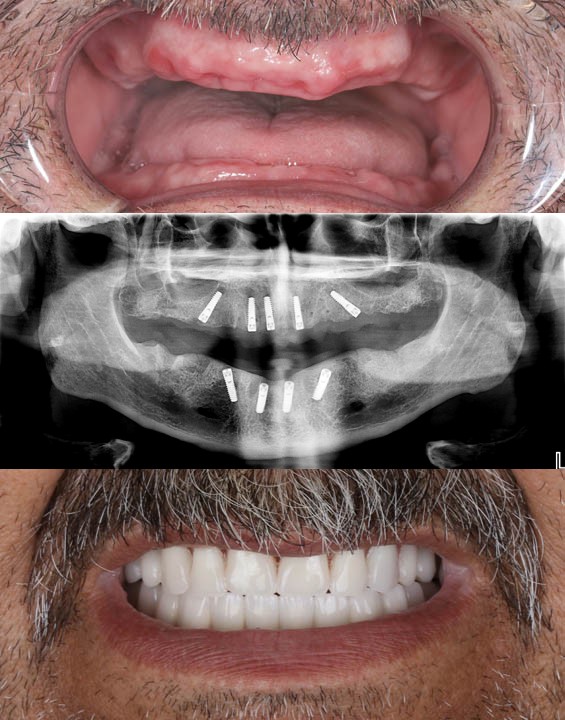

Full mouth reconstruction is a comprehensive process that restores all teeth in your mouth, addressing functionality and aesthetics. Unlike a smile makeover, which is primarily cosmetic, full mouth reconstruction is a necessary series of procedures designed to correct severe dental issues and restore long-term oral health.

🦷 Dental implants for long-lasting tooth replacement

🦷 Final placement of permanent restorations (crowns, veneers, inlays, onlays, bridges).